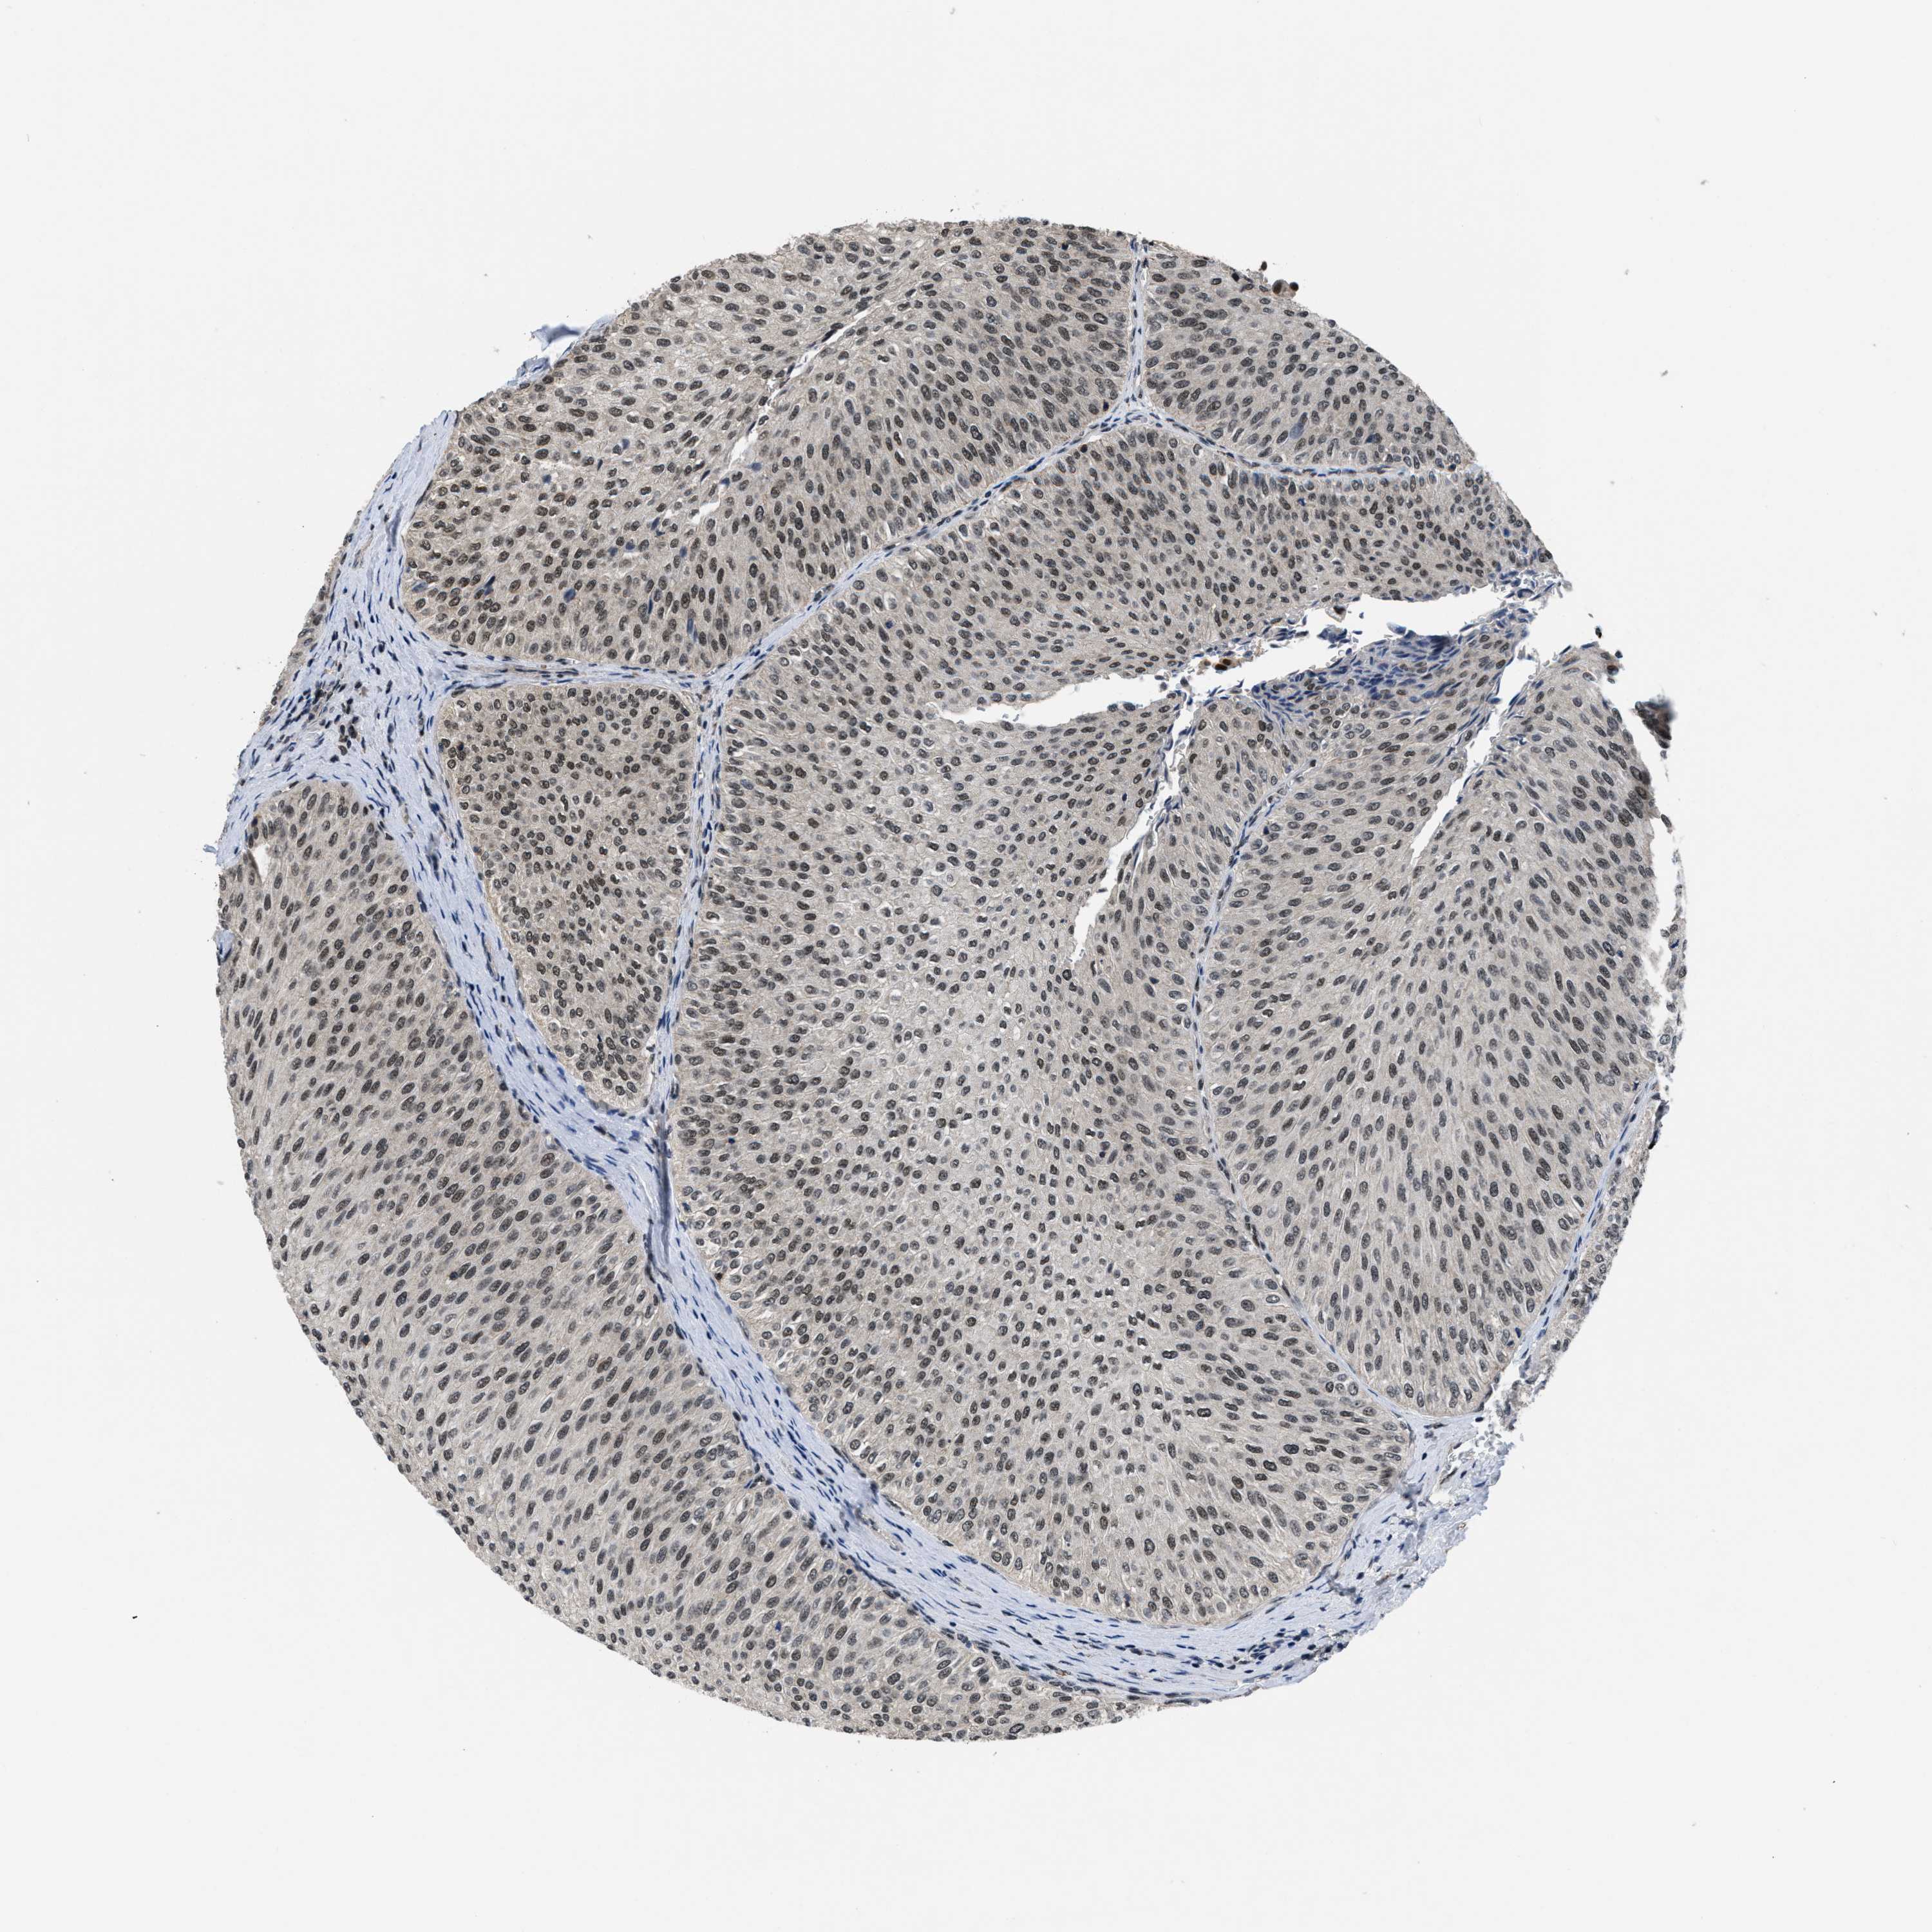

UROTHELIAL CANCER - Protein expressioni

A mouse-over function shows sample information and annotation data. Click on an image to view it in a full screen mode. Samples can be filtered based on level of antibody staining by selecting one or several of the following categories: high, medium, low and not detected. The assay and annotation is described here.

Note that samples used for immunohistochemistry by the Human Protein Atlas do not correspond to samples in the TCGA dataset.

Antibody stainingi

Antibody staining in the annotated cell types in the current human tissue is reported as not detected, low, medium, or high, based on conventional immunohistochemistry profiling in selected tissues. This score is based on the combination of the staining intensity and fraction of stained cells.

Each image is clickable and will lead to virtual microscopy that enables deeper exploration of all samples and also displays staining intensity scores, fraction scores and subcellular localization as well as patient and tissue information for each sample.

Antibody HPA011880

Antibody CAB017786

Staining

High

Medium

Low

Not detected

Intensity

Strong

Moderate

Weak

Negative

Quantity

>75%

75%-25%

<25%

None

Location

Nuclear

Cytoplasmic/membranous

Cytoplasmic/membranous,nuclear

Urothelial carcinoma, Low grade

Urothelial carcinoma, High grade